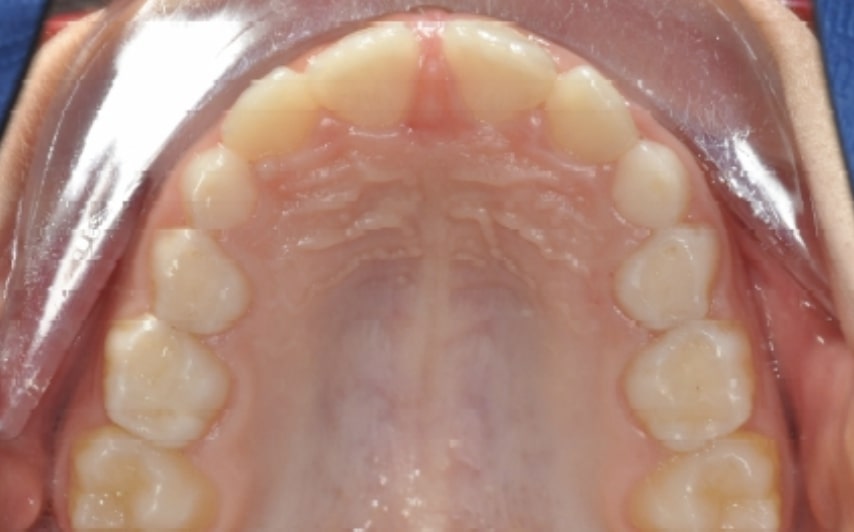

Initial Photos and datas

Clinical examination and diagnosis

• Reduced Transversal Diameters

• Upper Archform enlargement (dental expansion)